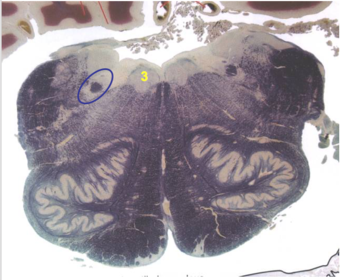

| CN IV | |

| Trochlear decussation | |

| Locus Coeruleus | |

| Mesenphalic V tract and nucleus | |

| Periventricular gray | |

| Inferior colliculus | |

| Lateral lemniscus | |

| Medial lemniscus | |

| ALS | |

| Ventral trigeminothalamic tract | |

| MLF | |

| Mesencephalic V tract and nucleus | |

| CN IV nucleus | |

| CN IV tract fibers | |

| Cerebral aquaduct | |

| Periaquaductal gray | |

| Decussation of superior cerebellar peduncle | |

| Pontine nuclei | |

| Cerebral peduncles | |

| Central tegmental tract | |

| Superior colliculus | |

| Brachium of the inferior colliculus | |

| Decussated superior cerebellar fibers | |

| Red nucleus | |

| Substantia nigra | |

| CN III nucleus | |

| CN III rootlets | |

| Edinger-Westphal nucleus | |